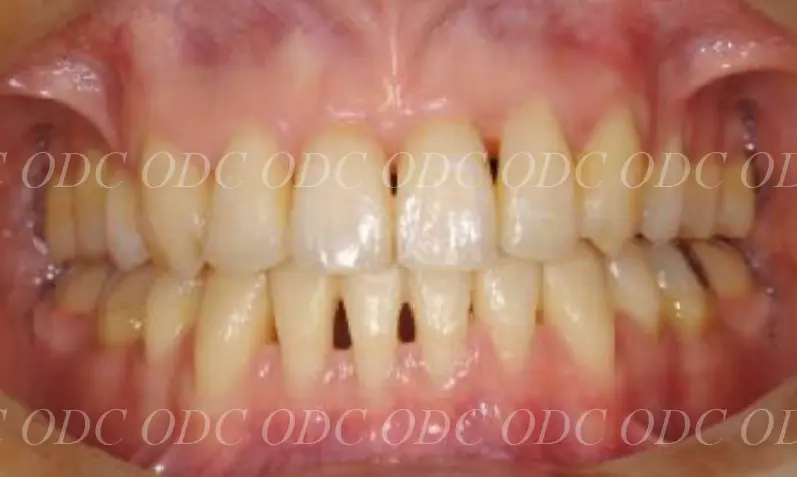

2011年、噛めないという主訴で65歳の男性が来院されました。

全顎的な治療を希望されていましたので、口腔内はもちろん骨格・顔貌・顎関節の診断を行い治療目標を設定致しました。

上顎天然歯に関しては矯正治療、下顎にはフルマウスのインプラント治療を計画致しました。

顎関節の安定を確認した後、矯正治療とインプラント治療を並行して行いました。

約3年の治療期間を経て、計画通りの満足のいく結果を獲得することができました。

2014年、治療終了時の口腔内の状態です。

インプラント上部構造はCADCAMによって作成されたジルコニアの上部構造です。

2024年、治療終了後約10年が経過いたしました。

顎関節を考慮した包括的な治療を行うことで咬合状態(噛み合わせ)は現在もとても安定した状態です。